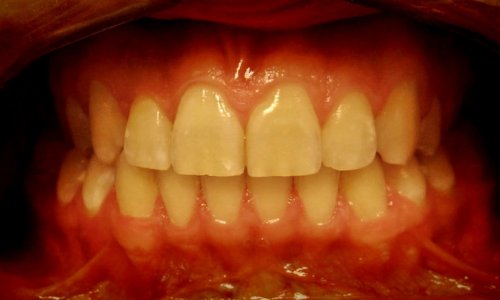

Stan Przed Leczeniem

Stan Początkowy

Stan wyjściowy: Pacjent zgłosił się z problemami estetycznymi i czynnościowymi zgryzu.